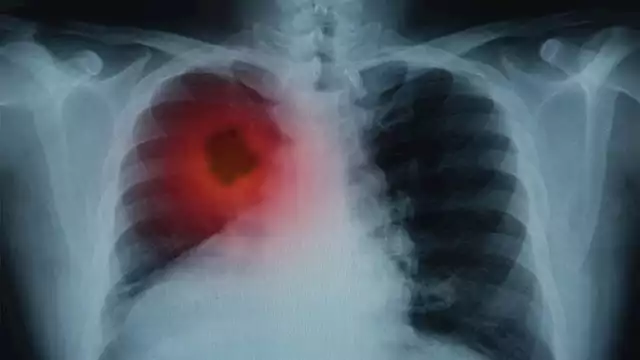

دراسة حديثة تشرح الأسباب وراء الانتشار السريع لسرطان الرئة ذو الخلايا الصغيرة

كشف فريق بحثي ألماني عن آلية بيولوجية جديدة تساهم في فهم السلوك العدواني لسرطان الرئة ذو الخلايا الصغيرة وتفتح آفاق جديدة للعلاج والتشخيص. وتُعَدُ هذه النتائج خطوة مهمة نحو تحسين فرص البقاء على قيد الحياة عبر استهداف مسارات حاسمة في تطور الورم وتفاعله مع الجهاز المناعي.